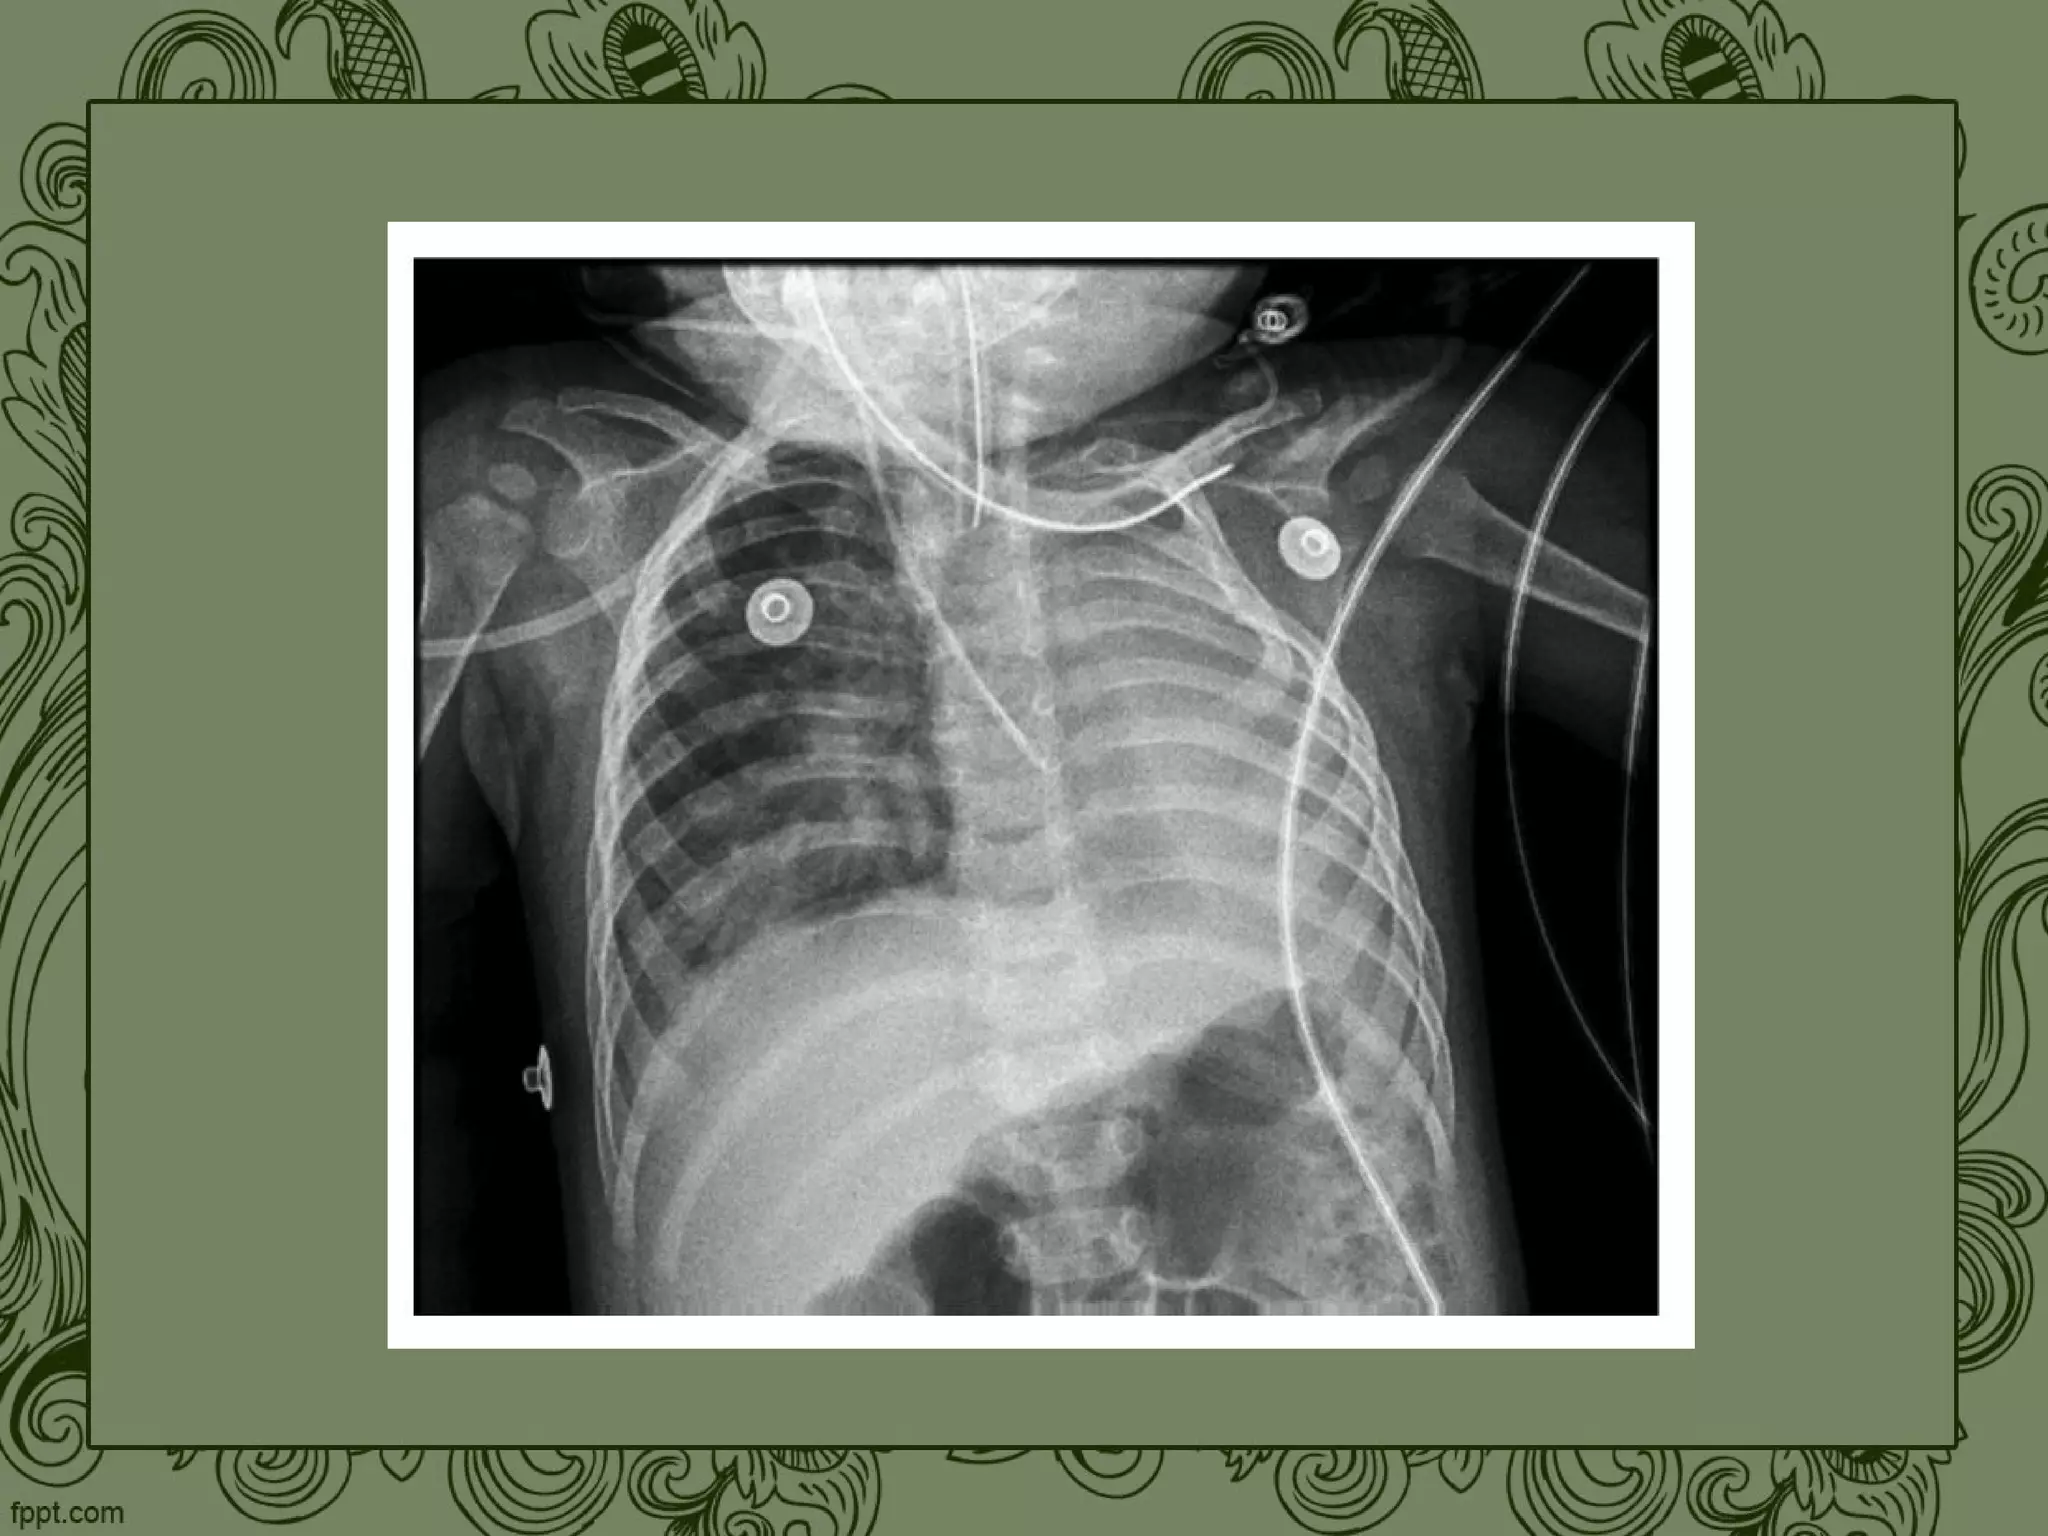

Аплазія та гіпоплазія легень. Дефіцит альфа-1-антитрипсину.